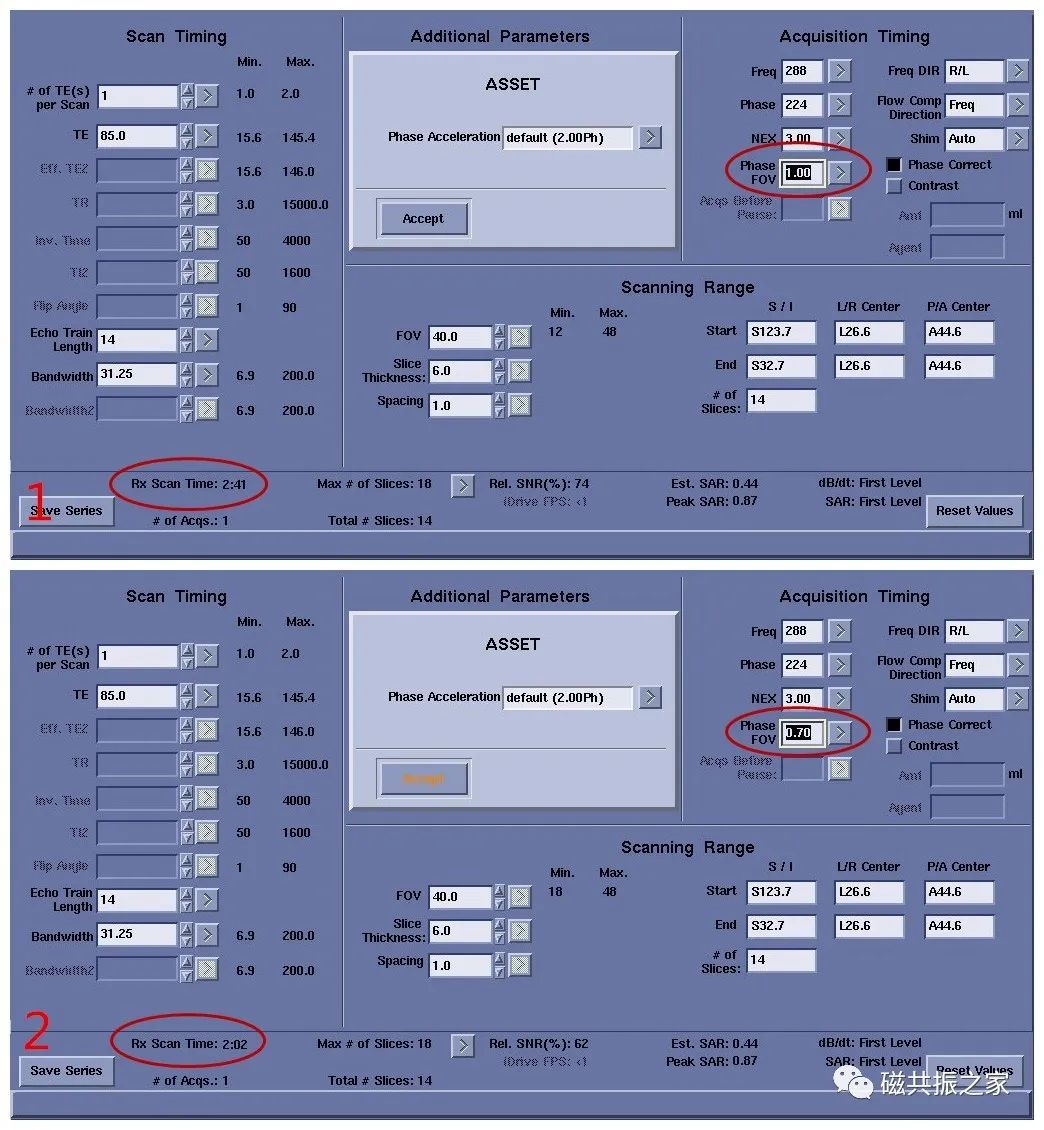

相位 FOV

图1,Phase FOV为1时,扫描时间为2:41,图2,Phase FOV为0.7时,扫描时间为2:02。选择为1.0时,在相位编码方向上采集全部的信号;选择0.9时 ,为采集90%信号,周边作填零处理;选择0.8时,为采集80% 信号……这样做的好处就是节省了扫描时间,几乎不牺牲信噪比及分辨率。矩形像素与其类似。